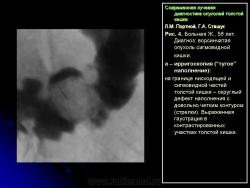

1) утолщение стенки, неровность контура и сужение просвета одного из участков кишки (рис. 5);

2) сохранение на расправленной от естественной складчатости поверхности слизистой кишки небольшого участка бариевой взвеси (типа звездочки или другой конфигурации) диаметром от 0,5 до 1,5 см – симптом ранних признаков опухоли (рис. 6);